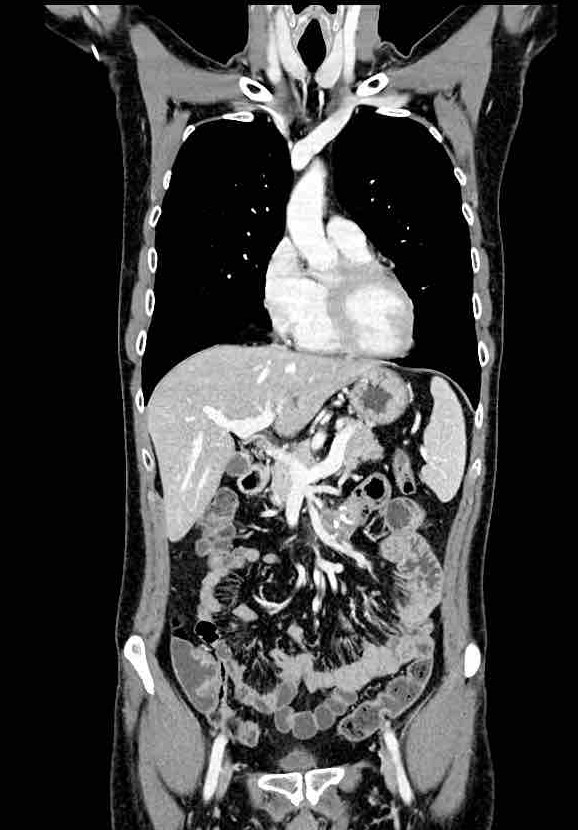

Nou hebben ze op een foto laten zien waar de tumor zit, daar stond ook een meet-lijn waardoor je de grootte kan zien. Hij is dus 2,2 cm en 6 weken geleden nog 3,4, het gaat dus goed. Verder houden we ons gewoon aan wat ze allemaal zeggen en gaan we gewoon mee in het advies.

Hierbij de foto’s:

En dat is ook zo, want op deze foto is te zien waar hij ligt (lieten ze ons zien)

In het midden zit een mooie stip (ader) En daar schuin boven zie je nog wat lichts (ook ader). Daar tussen zit een grijze klodder… dat is ‘m. De witte delen zijn aders, en daar moet hij dus los van komen te liggen.